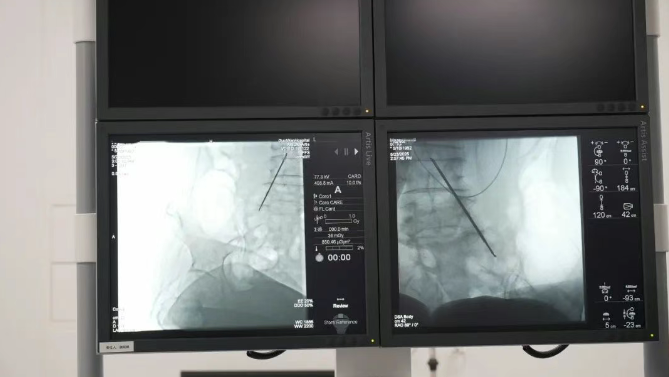

精準靶向,直擊疼痛根源鞘內(nèi)泵植入技術(shù)通過微創(chuàng)手段,將一枚微型鎮(zhèn)痛泵植入體內(nèi),經(jīng)導管精準連接至脊髓蛛網(wǎng)膜下腔(鞘內(nèi))。這一“生物鎮(zhèn)痛開關(guān)”可直接將鎮(zhèn)痛藥物輸送至中樞神經(jīng)系統(tǒng),相較傳統(tǒng)口服或靜脈給藥,所需藥量僅為1/300,卻能實現(xiàn)更高效、更精準的疼痛控制,從根源阻斷疼痛信號傳導,讓患者徹底擺脫疼痛困擾。

長效緩釋,智能調(diào)控植入的鎮(zhèn)痛泵采用長效緩釋技術(shù),可持續(xù)穩(wěn)定釋放藥物,為患者提供24小時不間斷的鎮(zhèn)痛保護。同時,設備支持個性化智能調(diào)控,醫(yī)生可根據(jù)患者疼痛程度遠程或手動調(diào)整藥物劑量,確保鎮(zhèn)痛效果精準適配不同階段需求。一次植入,長期有效,無需頻繁用藥,極大減輕患者身體與心理負擔。